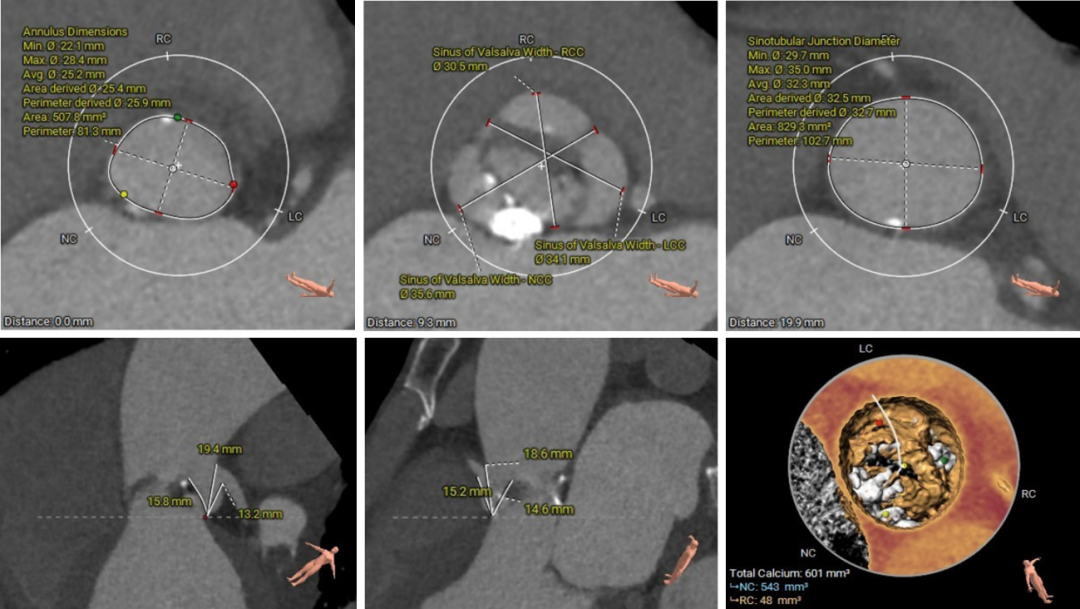

主动脉根部评估及手术策略制定:

1.瓣环周长84.4mm,平均周长径26.9mm;

2.SOV瓦式窦周长114.6mm,平均周长径36.5mm ;

3.LVOT 周长95mm,平均周长径 30.3mm;

4.STJ 周长103.3mm,平均周长径 32.9mm,高度20.4mm。

手术策略制定:

1.CT三维评估表明为Type1二叶式主动脉瓣,左窦与右窦瓣叶融合,无冠窦有重度团块样钙化。

2.左右冠脉开口高度可,且左右瓣叶在高位融合处有明显的增厚,术前经手术团队进行评估,相应冠脉风险较低。

3.拟采用22mm球囊进行预扩,植入TaurusElite AV26瓣膜,使用Cusp-Overlapping技术零位或高危释放的策略降低术后新发传导阻滞风险。